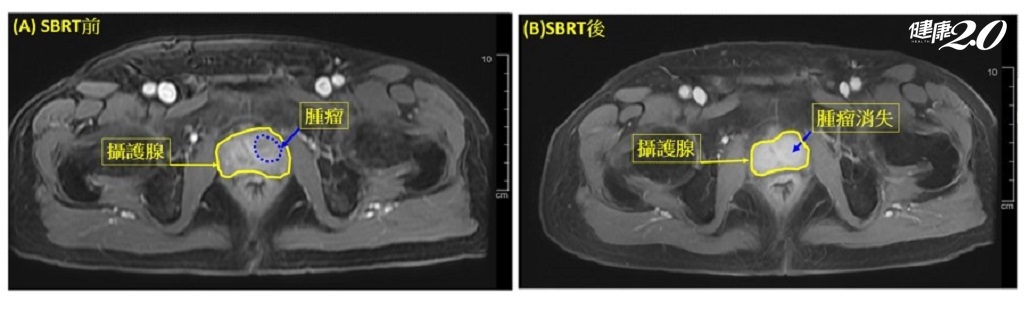

經過與醫療團隊的共享決策模式(SDM),林先生選擇接受僅需5次療程的SBRT治療,而非傳統的20次或39次放射療程。這項選擇不僅減少了治療的時間,也降低了副作用的風險。經過治療後一周,林先生的PSA值顯著下降,治療兩個月後PSA值再度降低,並通過磁振造影證實腫瘤已完全消失。林先生感激醫療團隊的專業,並表示治療後能夠迅速恢復正常生活,重拾健康與信心。

◎ 圖片來源/亞東醫院提供